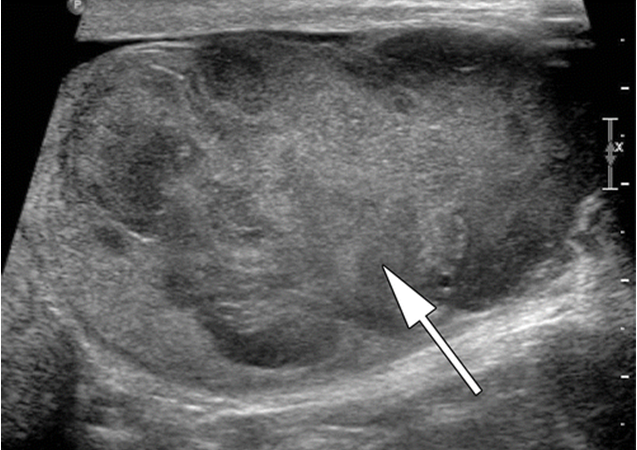

Ультразвуковое исследование (УЗИ) мошонки является предпочтительным начальным визуализирующим исследованием для оценки образования яичка. УЗИ может подтвердить наличие новообразования, определить его расположение и оценить состояние противоположного яичка (рис. 4). Чувствительность метода достаточно высокая – от 92 % до 98 %.

Снимок УЗИ яичка